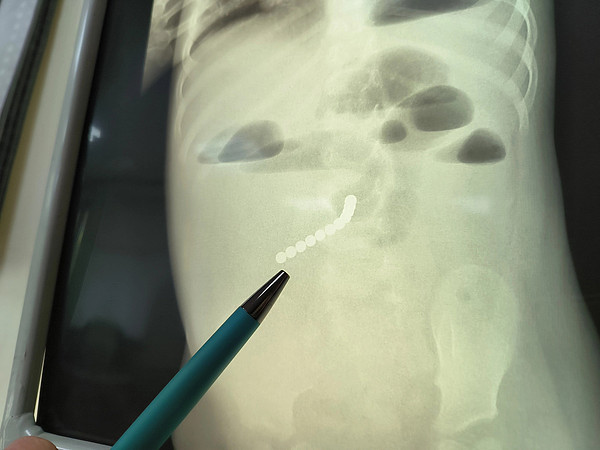

Порядка 8 тысяч исследований провели рентгенологи Кировской детской областной больницы с начала 2023 года